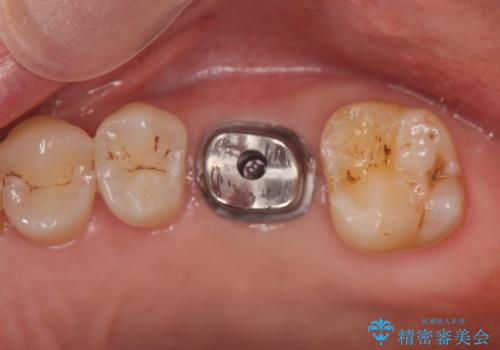

奥歯の欠損 インプラントによる咬合機能回復

- 奥歯を失い噛めないことの治療を希望され来院されました。

臨在する歯が虫歯もなく健全であるため、ブリッジではなくインプラントを用いた機能回復を計画します。

- 50万円(ストローマンインプラント・骨造成・チタンカスタムアバットメント・ジルコニアクラウン)費用は治療当時の料金となります

インプラントを用いることで、隣の歯を削ることなくしっかりと噛む機能を回復させることができます。